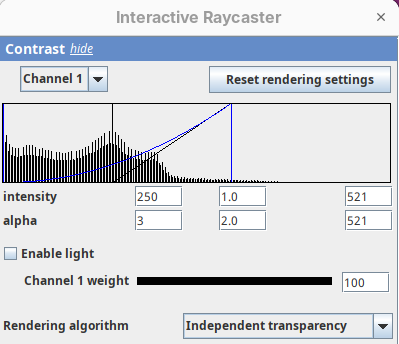

Contrast

The Contrast section shows a histogram of pixel intensities of the image for each channel, which we can choose using the dropdown menu. We can set the minimum, gamma, and maximum values for the intensity and alpha (transparency) properties of each pixel. The weight option controls the general opacity of the channel (0=invisible, 100=visible). There’s also more advanced options like lighting and rendering algorithm which we’ll simply use the default states as they are usually good for most use cases.

Adjusting the intensity and alpha values is the most impactful way to improve the 3D rendering. With the intensity setting we can define which pixel value in the image corresponds to total black (minimum) and which corresponds to total white. It’s the same as in the standard Brightness & Contrast tool. By default, 3Dscript will load these values from the original stack. In this case, it loaded min=3 and max=521.

Let’s change these values to see how it impacts the 3D rendering.

- Change the intensity minimum to

250.

You will see that the darkest parts of the rendering will become even darker and no longer visible. We are losing real information from the data; we do not want that.